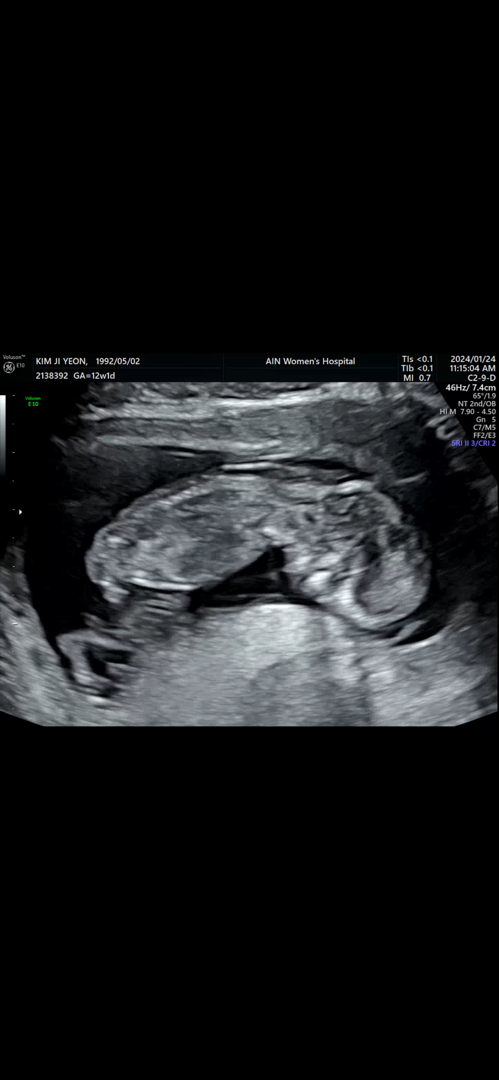

12주 초음파 보고 왔는대 성별 예측 가능하신분들 계실까요 ㅎㅎㅎㅎ